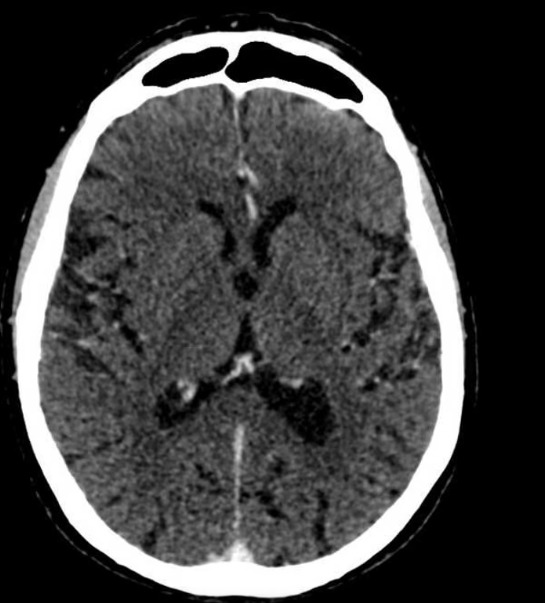

脑肿瘤

血管神经放射学

血管和脑卒中影像

- 脑卒中影像 — 快速准确判读

- 动脉瘤和血管畸形诊断

- 血管神经放射学专业知识